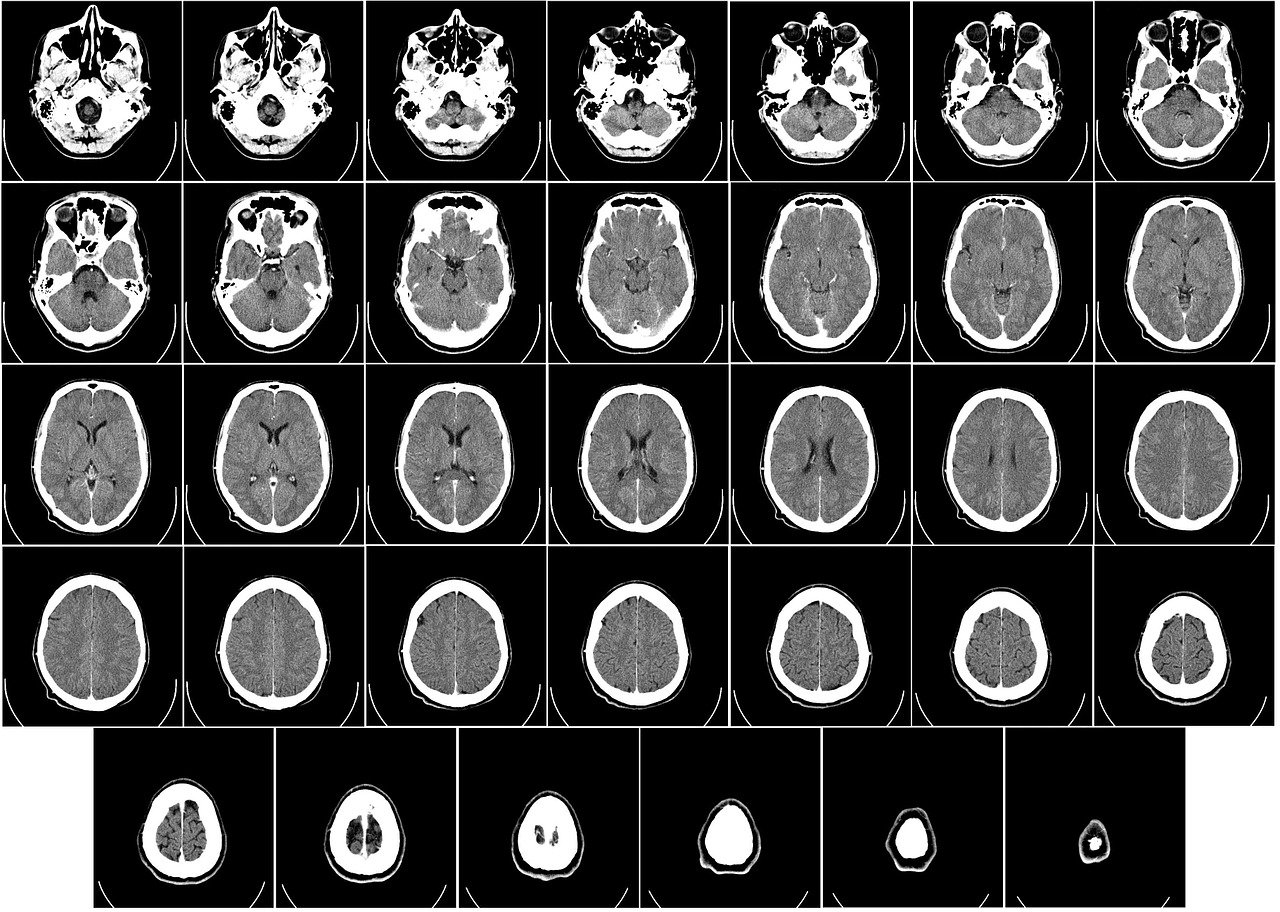

3) 영상 검사

- CT 또는 MRI 촬영 : 뇌졸중, 종양, 염증 등의 원인을 확인하기 위해 뇌의 이미지를 촬영합니다.